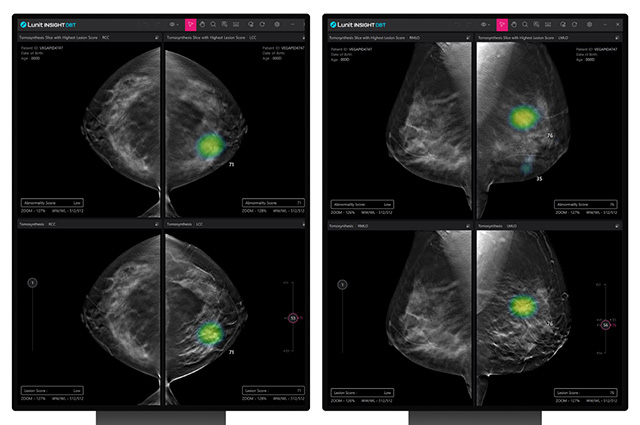

‘루닛 인사이트 DBT’는 디지털 유방단층촬영술(DBT)로 얻은 3차원 유방 영상을 AI로 분석해 의료진의 판독을 보조하는 솔루션이다. 해당 솔루션은 기존 2차원 유방촬영술보다 병변을 입체적으로 파악할 수 있어, 치밀 유방을 가진 환자에 대한 진단 정확도를 높일 수 있는 것이 특징이다.

• Lunit INSIGHT DBT /이미지 제공=루닛

▲ Lunit INSIGHT DBT /이미지 제공=루닛